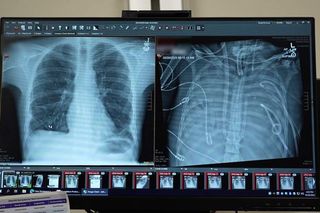

The monitor screen, as it tracks oxygen, blood flow, and temperature, as the artificial lung system replaces the lung function of the infected lungs.

(Image Credit: Northwestern Medicine CC by SA)